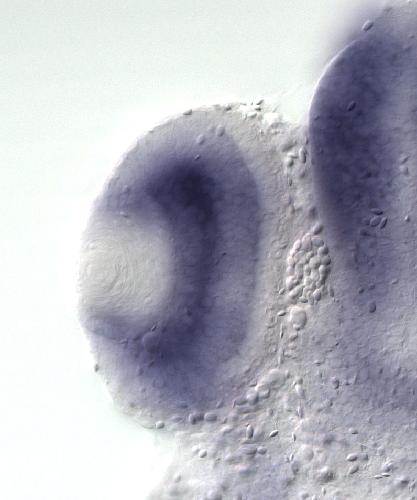

???displayGene.symbol???: lrba

???displayGene.name???: LPS-responsive vesicle trafficking, beach and anchor containing

???displayGene.geneFunction??? Kinase A-anchor protein Neurobeachin and related BEACH and WD40 repeat proteins Protein Function

Diseases: Disease Ontology: common variable immunodeficiency